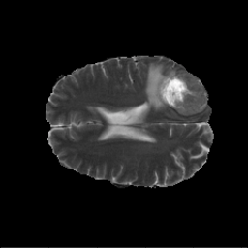

BraTS2018

This dataset comes from the Multimodal Brain Tumor Segmentation Challenge 2018 [4, 5, 35] and contains multi-parametric magnetic resonance imaging (mpMRI) scans of low-grade glioma (LGG) and high-grade glioma (HGG) patients. There are 210 HGG and 75 LGG cases in the training data, and each case has four types of MRI scans and three types of tumor subregion labels. In our experiments, we perform 2D segmentation on T2 images of the HGG cases to extract the whole tumor regions. The 2D slices with tumor areas smaller than 10 pixels are excluded for both GAN training and segmentation phases. In the GAN synthesis phase, all three labels are utilized to generate fake images. For segmentation, we focus on the whole tumor (regions with any of the three labels).

There are 210 HGG cases in the training data. Because we have no access to the test data of the BraTS2018 Challenge, we split the 210 cases into train (170 cases) and test (40 cases) sets. The train set is then sorted according to the tumor size and divided into 10 subsets equally, which are treated as data in 10 distributed medical entities. There are 11,057 images in the train set and 2,616 images in the test set. We conduct the following segmentation experiments: (1) Real-All. Training using real images from the whole train set (170 cases). (2) Real-Subset-n. Training using real images from the -th subset (medical entity), where . There are 10 different experiments in this category. (3) Syn-All. Training using synthetic images generated from a regular GAN. The GAN is trained directly using all real images from the 170 cases. (4) AsynDGAN. Training using synthetic images from our proposed AsynDGAN. The AsynDGAN is trained using images from the 10 subsets (medical entities) in a distributed fashion.

In all experiments, the test set remains the same for fair comparison. It should be noted that in the Syn-All and AsynDGAN experiments, the number of synthetic images are the same as that of real images in Real-All. The regular GAN has the same generator and discriminator structures as AsynDGAN, as well as the hyper-parameters. The only difference is that AsynDGAN has 10 different discriminators, and each of them is located in a medical entity and only has access to the real images in one subset.

(a) Image

(b) Label

(c) Real-All

(d) Syn-All

(e) Real-Subset-6

(f) AsynDGAN

(a) Input

(b) AsynDGAN

(c) Real

4.4.2 Results

The quantitative brain tumor segmentation results are shown in Table 2. The model trained using all real images (Real-All) is the ideal case that we can access all data. It is our baseline and achieves the best performance. Compared with the ideal baseline, the performance of models trained using data in each medical entity (Real-Subset-110) degrades a lot, because the information in each subset is limited and the number of training images is much smaller.

Our AsynDGAN can learn from the information of all data during training, although the generator doesn’t “see” the real images. And we can generate as many synthetic images as we want to train the segmentation model. Therefore, the model (AsynDGAN) outperforms all models using single subset. For reference, we also report the results using synthetic images from regular GAN (Syn-All), which is trained directly using all real images. The AsynDGAN has the same performance as the regular GAN, but has no privacy issue because it doesn’t collect real image data from medical entities. The examples of synthetic images from AysnDGAN are shown in Figure 5. Several qualitative segmentation results of each method are shown in Figure 4.